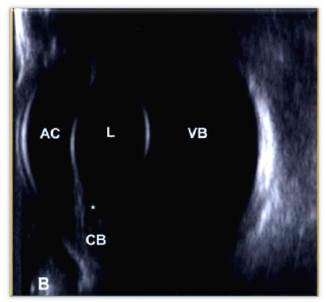

Cuando se habla de ecografía ocular es importante realizar comparación del ojo contra lateral, siempre que sea posible, diferenciando las distintas estructuras oculares como lo son: cornea, cámara anterior, lente (cristalino), cuerpo ciliar, cámara posterior, cámara vítrea, retina y nervio óptico (Figura 9) 10. Además de realizar diferentes cortes: longitudinales, transversales y axiales que permitan diferenciar posibles anormalidades, su ubicación y medida.

Comparando con el caso clínico, y de acuerdo a lo reportado en la bibliografía se puede observar que el ojo izquierdo está ecográficamente normal (Figuras 10 y 11), ya que se identifican todas las estructuras anatómicas normales, sin ningún tipo de alteración.